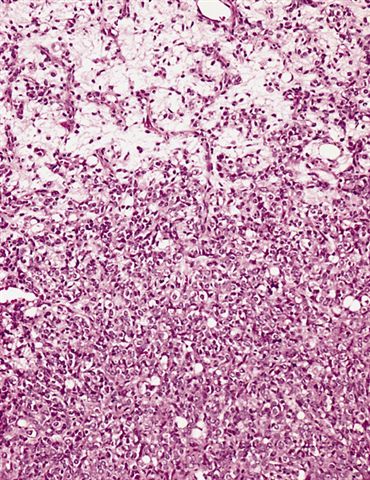

- High grade

- Hypercellular solid sheets of back to back cells with round cell or primitive cytomorphology in > 5% of the sampled tumor

- Cells can have a small amount of hypereosinophilic cytoplasm, a finding of no clinical significance but of significant diagnostic confusion, especially in a limited sample

- Pitfalls and tips

- High grade tumors are so cellular that you can typically walk across nuclei in a high power field without stepping in matrix